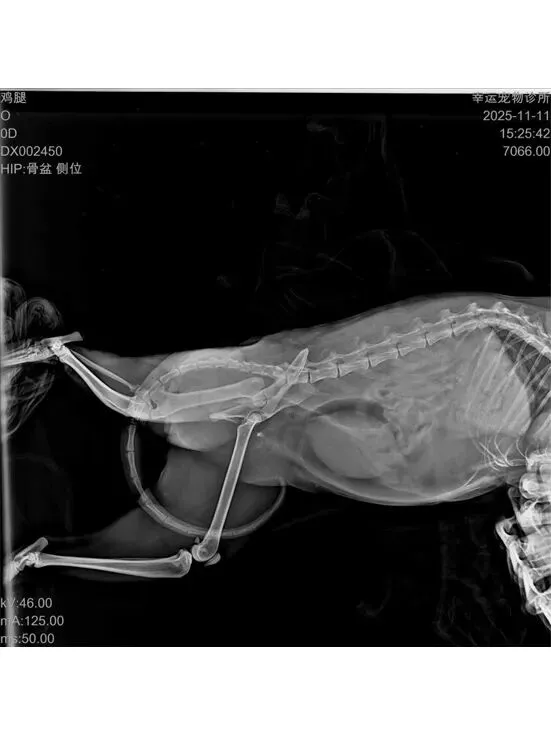

志愿者发现鸡腿蜷缩在楼梯底下不断嚎叫,且后腿无法动弹,于是当天抓捕送医。

就医检查:鸡腿后肢在医生被触摸时仍有痛觉反应,经判断大概率为盆骨骨折,且右后脚带有明显伤口,具体情况需拍摄X光片来确定。鸡腿连袋重:4.95kg。

盆骨X光片:盆骨粉碎性骨折,因十号的生化血常规和SAA指标达标,于是准备12号进行手术。

由于只因应激导致心脏骤停的情况较为罕见,医生在事后继续完成未进行的心超检查,发现鸡腿极有可能是因为原本存在的气胸漏液渗到肺部,从而导致肺部受压、供氧不足,加上因环境变化产生的应激,最终引发心脏骤停。以上情况表明,鸡腿极有可能在10号或者10号之前就存在肺部损伤,类似外伤引起肺挫伤。